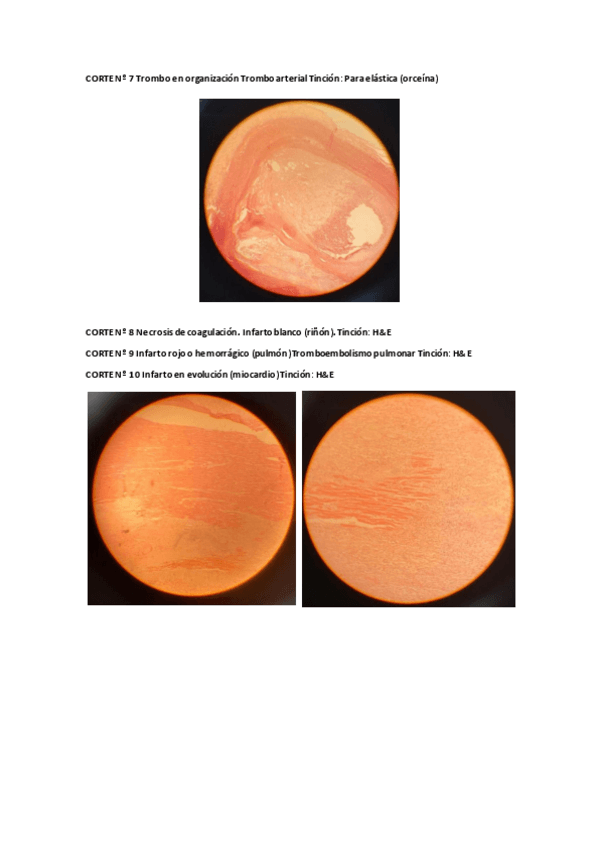

Practicas-APPortas-6-10.pdf